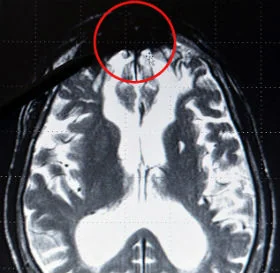

الأمر الذي دعا البروفيسور للقيام بأبحاث ودراسات عديدة بالتعاون مع فريق ينمكمكنمنمكنمنضم عدة باحثين في طب الأعصاب وقد قام جيرهارد بعرض شريط فيديو تظهر فيه أعمال عنف وحشية على مجرمين ارتكبوا أعمال إجرامية متنوعة واحداً تلو الآخر ومن ثم قياس أنشطتهم الدماغية والكشف عليها بالأشعة السينية فوجد أن جميع أجزاء الدماغ تتفاعل مع ما ترى إلا جزء واحد بقي راكداً بلا أي تفاعل ، ورغم وجود هذا الجزء الذي سماه " البقعة المظلمة " فقد تم تداوله إعلامياً باسم علامة الشر أو الشيطان، أي المركز الذي يصدر الاوامر الشريرة لدى الإنسان.